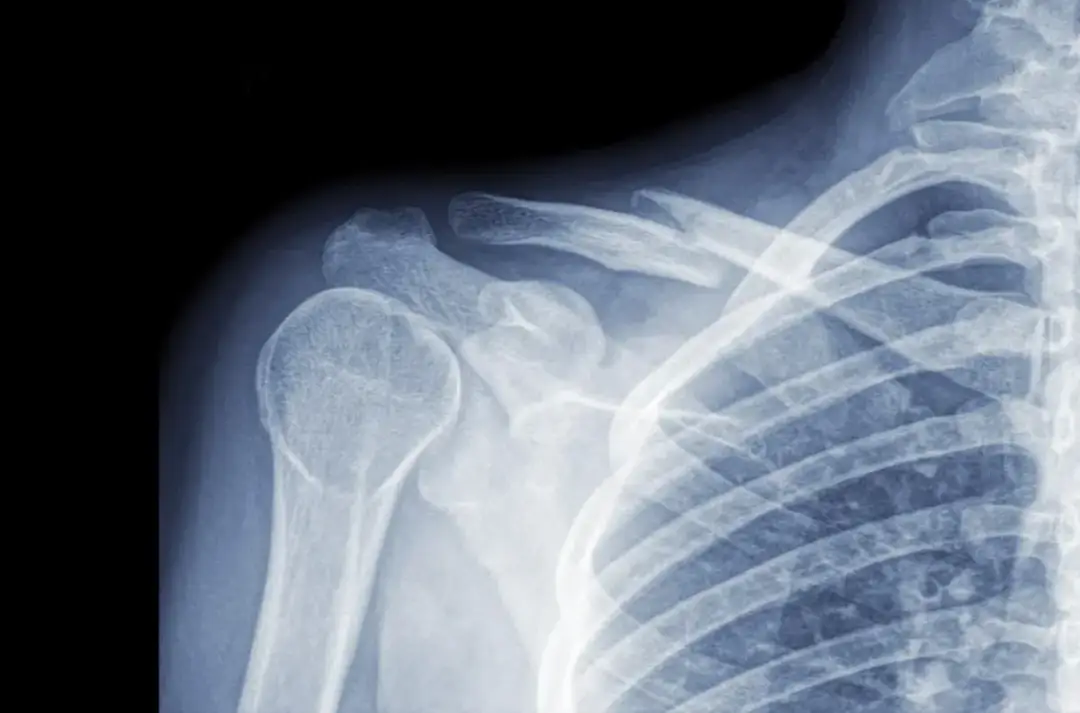

Złamany obojczyk u dziecka? Poznaj objawy, metody diagnostyki i skuteczne leczenie. Dowiedz się, jak rozpoznać uraz i zapewnić właściwą opiekę swojemu dziecku.